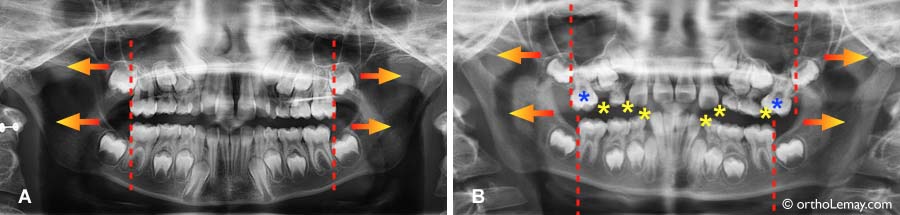

espace pour eruptions

Ces exemples montrent l’importance de préserver l’espace disponible pendant l’éruption des dents et le fait que la croissance aide… mais pas nécessairement où sont situés les problèmes d’encombrement dentaire et de manque d’espace. Une supervision adéquate pendant le développement dentaire permettra de minimiser les problèmes d’espace et d’éruption.

Les radiographies ci-dessous illustrent ce phénomène :

(A) Cette jeune fille de 8 ans manque d’espace pour l’éruption des dents permanentes postérieures. La croissance résiduelle des mâchoires se produira à l’arrière des premières molaires (pointillé rouge) dans la direction des flèches.

(B) Ce garçon de 9 ans a déjà perdu beaucoup d’espace dans les régions indiquées par des astérisques jaunes (*). Les premières molaires supérieures (* bleues) ont même migré vers l’avant, réduisant la longueur de l’arcade dentaire. La croissance des mâchoires n’aidera pas ce manque d’espace en se produisant derrière les molaires permanentes.